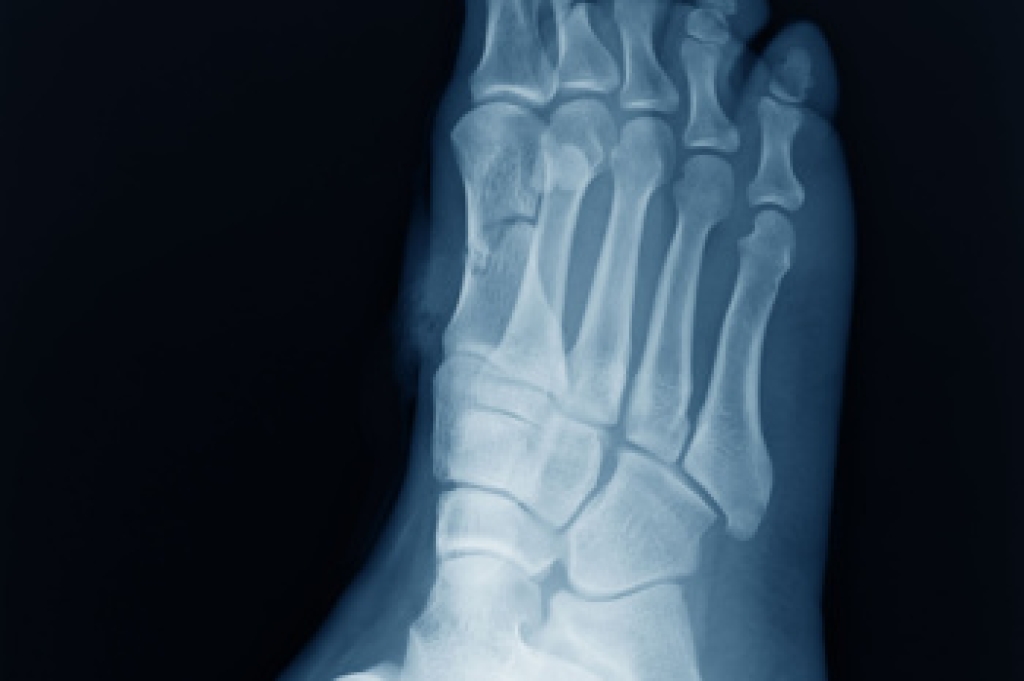

In order to diagnose your bunion, your podiatrist may ask about your medical history, symptoms, and general health. Your doctor might also order an x-ray to take a closer look at your feet. Nonsurgical treatment options include orthotics, padding, icing, changes in footwear, and medication. If nonsurgical treatments don’t alleviate your bunion pain, surgery may be necessary.